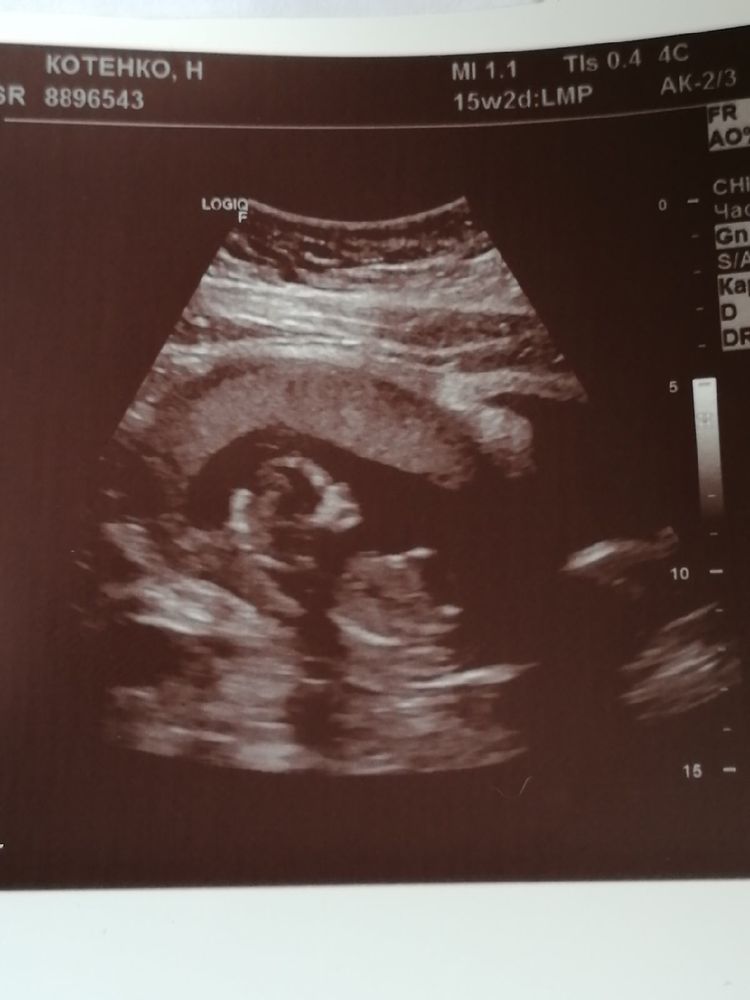

14 недель. УЗИ + фото малыша)

УЗИ, КТГ, доплерВсе таки сходила я на УЗИ, дабы успокоиться и посмотреть на крошку. Мы уже такие большие, оказывается) Малыш опять во всю сосал пальчик, а еще увидела, как он икает 🥰 Партизан не захотел показывать свои прелести, скрестил ножки и отвернулся от нас 😄 Узист сказала, что профиль прям аккуратненький, как у девочки) Но не хочу раньше времени надумывать, будь кто будет, главное здоровый ❤ Может тут есть те, кто может предположить по профилю, кто это у нас?)